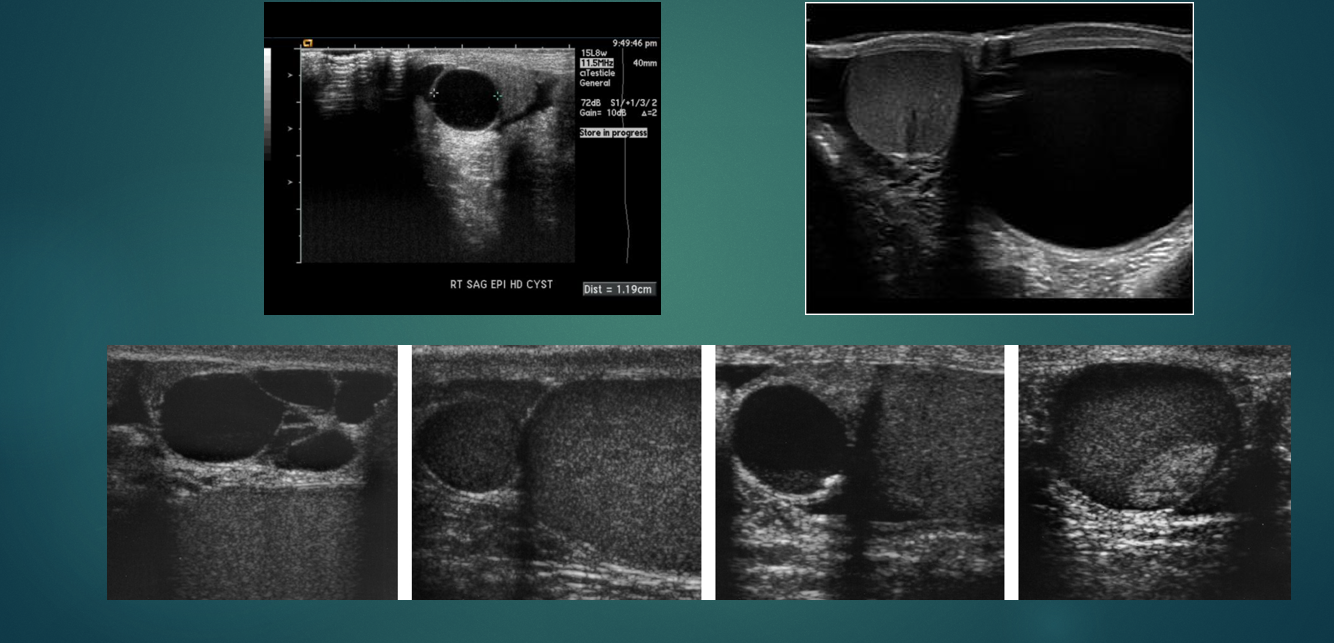

Epididymal cyst- US

what is this image showing

abscess